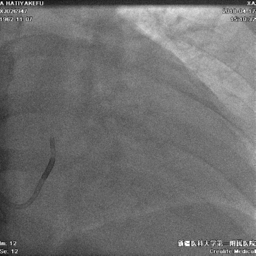

冠状窦寻找

● 使用强生十极寻找冠状窦后,顺势推送长鞘进入冠状窦内

冠状静脉造影

● 冠状静脉造影,选择靶血管侧静脉。血管远端无法看清,使用鞘中鞘造影靶血管

鞘中鞘超选靶血管造影

● 根据造影结果尝试选择侧静脉